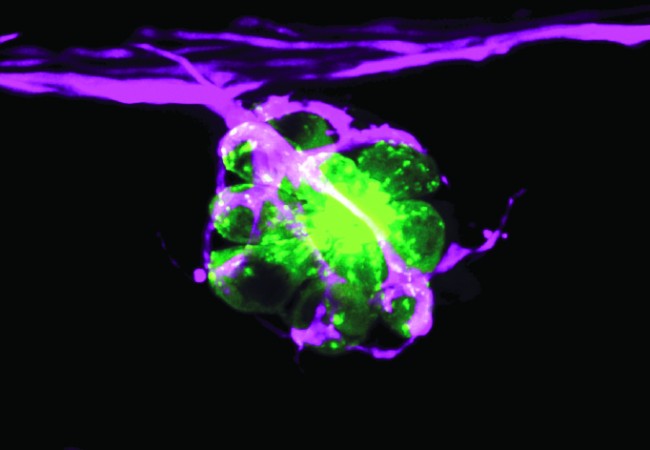

腸オルガノイド

The Francis Crick Institute

ミニ腸に光を当てる 研究室の皿の中で培養されるヒト細胞は、科学者が発生や病気をモデル化するための重要な研究ツールです。オルガノイドは、科学者がヒトの臓器がどのように成長し、治療にどのように反応するかを調べることを可能にする、最近の生物医学研究のブレークスルーのひとつです。

これは、研究室でシャーレの中で培養されたオルガノイド(ミニ腸)の蛍光画像です。基本的に、幹細胞が3次元的に成長し、特定の臓器(この場合は小腸)の構造と機能を再現する小さな細胞塊を形成したものです。フランシスクリック研究所の幹細胞・癌生物学研究室の研究者たちは、腸オルガノイドを使って、健康な腸を維持するために幹細胞がどのようにプログラムされているのか、また癌化すると何がうまくいかなくなるのかを研究しています。

この画像は、さまざまな色の蛍光マーカーを腸オルガノイドに導入し、核など細胞のさまざまな部分を蛍光標識することで作成されました。共焦点顕微鏡を使い、科学者たちは蛍光分子をレーザーで励起させ、ミニ腸管構造のさまざまな領域を可視化し、識別できるようにしました。

これらの細胞が健康な腸でどのように機能し、腫瘍が発生するとどうなるかを理解することは、科学者たちが腸癌治療のための特効薬を開発するのに役立ちます。さらに、この知識を利用して、臓器移植や新薬の試験に使用するための代替ヒト腸組織を研究室で培養することもできます。

作者:Vivian Li Lab